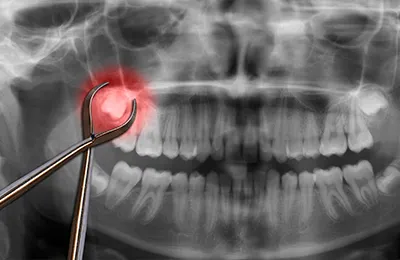

親知らずから顎の疾患まで幅広く対応する口腔外科治療

口腔外科は、お口の中やあご、顔まわりに関する外科的な疾患を扱う分野です。親知らずの抜歯や顎関節症、口の中のできもの、顎の骨折、口腔内の炎症や腫瘍など、一般の歯科では対応が難しい幅広い症状に対して専門的な診断と治療を行います。

とくに親知らずは、斜めや横向きに生えている場合や、歯ぐきの中に埋まっている場合には、他の歯に悪影響を与える可能性があるため、抜歯が必要となることがあります。一方で、問題がなければ無理に抜く必要はなく、正確な診査が重要です。また、顎がカクカクと鳴る、口が開きづらいといった症状がある患者様には、顎関節症の可能性があり、適切な検査と治療が必要です。